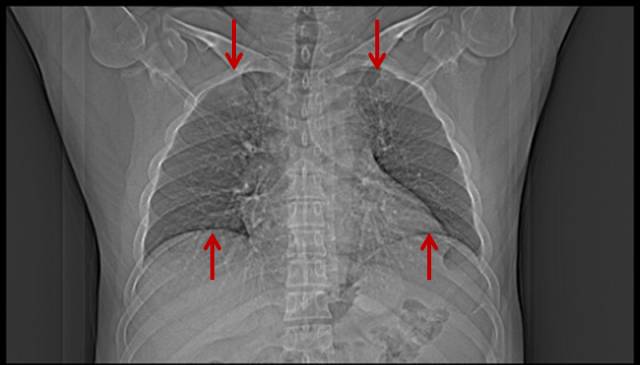

■肥胖体型吸烟者肺部改变

1.肥胖体型的吸烟者,因为腹部堆积大量的脂肪把膈肌抬高,如果用X线平片判断有无肺气肿,会直接漏掉。

男,46岁,16岁开始吸烟。